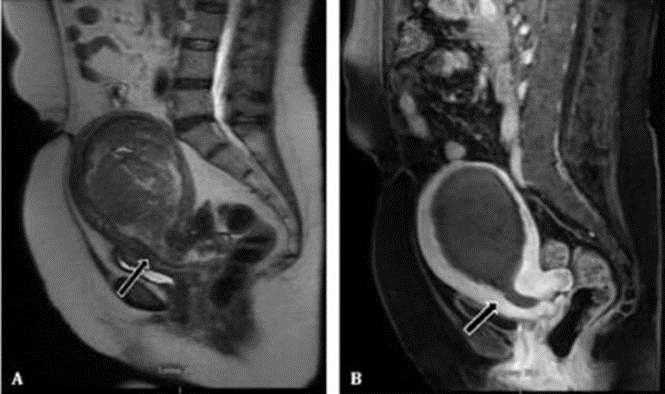

Pelvic MRI

A pelvic MRI scan specifically helps your doctor to see the bones, organs, blood vessels, and other tissues in your pelvic region—the area between your hips that holds your reproductive organs and numerous critical muscles. It can help find problems such as tumours in the ovaries, uterus, prostate, rectum, and anus. If you are pregnant, MRI may be used to safely monitor you or your baby. Excellent modality to diagnose endometriosis as MRI is sensitive to blood products.

Uterine artery embolization (UAE) is a procedure to treat fibroids without surgery. Instead, the doctor (a radiologist) uses special imaging methods to treat your uterine fibroids. During the procedure, the blood supply of the fibroids is cut off, causing the fibroids to shrink. Fibroids are non-cancerous growths that develop in or around the womb (uterus). The growths are made up of muscle and fibrous tissue, and vary in size. They're sometimes known as uterine myomas or leiomyomas. Many women are unaware they have fibroids because they don't have any symptoms.